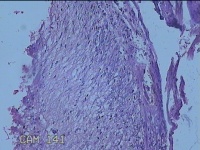

阑尾

性别

女

年龄

48岁

临床诊断

急性坏疽性阑尾炎 弥漫性腹膜炎

一般病史

转移性右下腹疼痛3天。

标本名称

大体所见

灰白暗红色阑尾2.5x0.8x0.3cm一条,表面糜烂,肿胀,带大量系膜,部分已切开,见腔内暗红色,另有灰褐色粪石1.9x0.7x0.3m一枚。